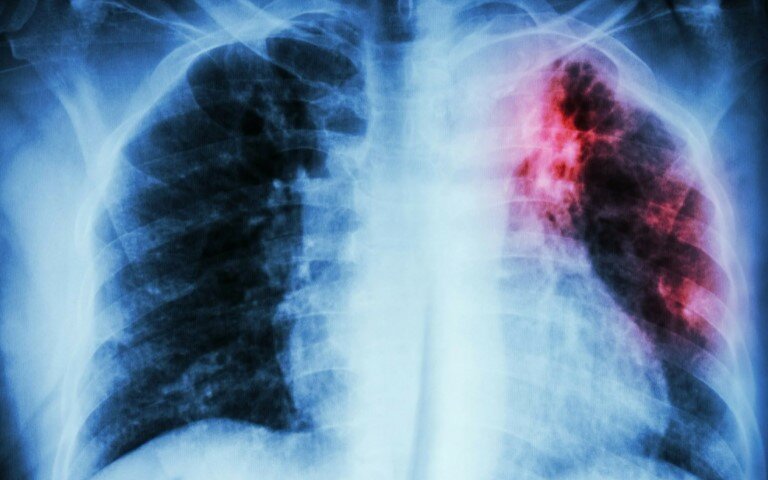

Туберкулез — это инфекционная болезнь, передаваемая воздушно-капельным путем.

Вызывают ее микобактерии, или палочки Коха. Они развивают воспаление тканей с образованием гранулём и очагов некроза, вследствие которых развивается общая интоксикация организма.

В основном, туберкулез поражает лёгочную систему, но может распространяться и на другие органы: костную ткань, кожные покровы, кишечник.

По статистическим данным, туберкулез находится в десятке самых частых причин смертности.